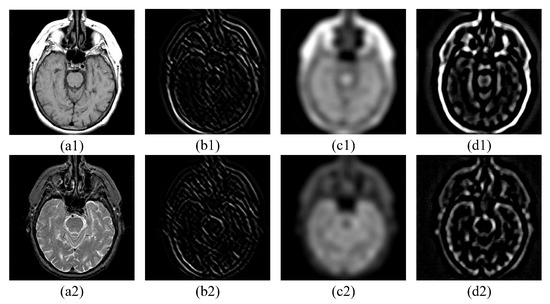

5.1.1. Experimental Images

5.2.1. Fusion Analysis on T1-T2

5.2.2. Fusion Analysis on T2-PD